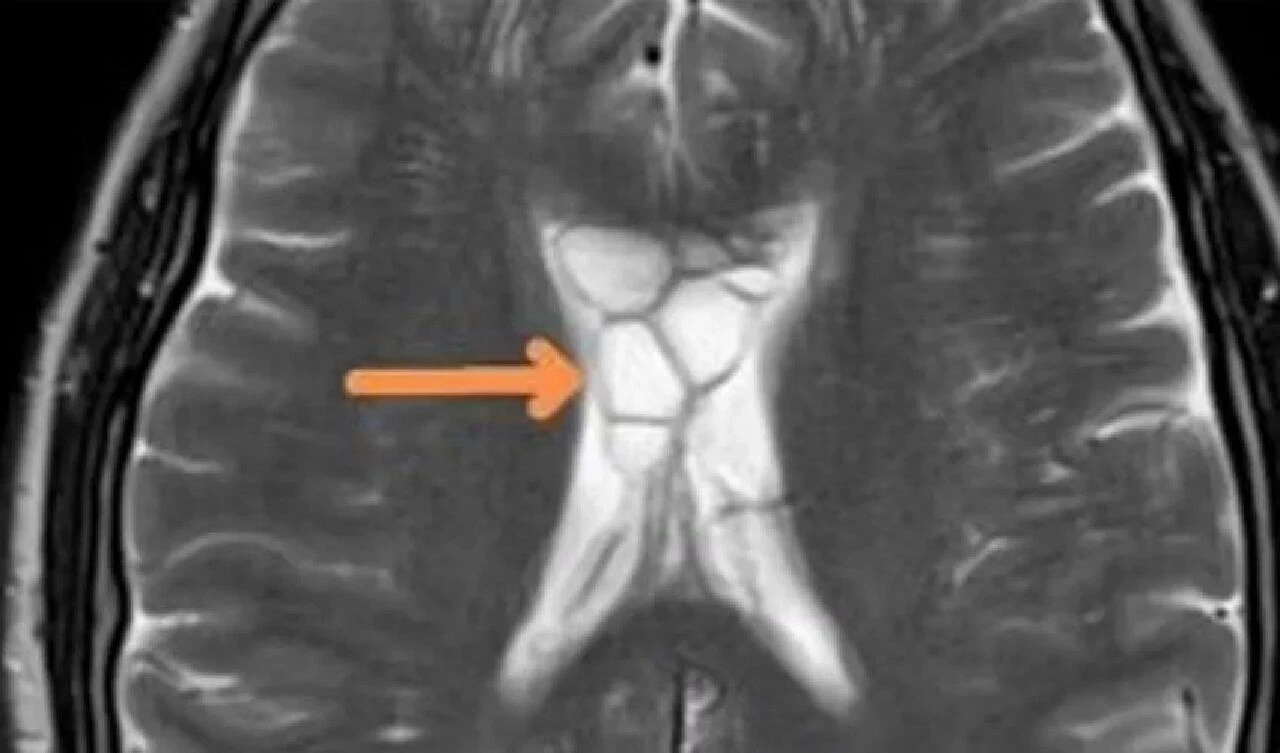

Doktorlar, kistlerin tenya yumurtaları olduğunu, tenyanın ise kafatasının altındaki dokuyu tahriş ettiğini söylediler. Hasta, yemek tercihlerinde az pişmiş eti sevdiğini söylemesiyle tenyanın vücuduna nasıl girdiği de ortaya çıkmış oldu.

Doktorlar, yaptıkları araştırmaların ardından adama nörosistiserkoz tanısını koydular. Bu tanı, tenyanın larva yumurtalarının vücudun çeşitli yerlerinde görülmesinin ardından konuldu. Uzmanlar, tenya parazitinin, hastanın az pişmiş eti yedikten sonra vücuduna girdiğini kan dolaşımı sayesinde beyne doğru ilerlediğini düşünüyorlar. Sağlık görevlileri, "Hastanın hayatı boyunca az pişmiş et tercih etmesi bu duruma yol açmış olabilir" dedi.